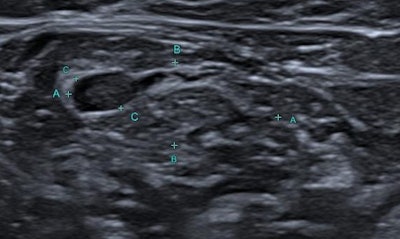

The researchers divided the lymph nodes into three groups depending on the type of cortical thickening as diffuse, closer (eccentric cortical thickening on the side near the tumor and/or breast) and distant (thickening on the further side) asymmetry. For each lymph node, the researchers recorded longitudinal to transverse axis (L/T) ratio, the largest cortical thickness, C/H ratio, hilar status (normal/displaced/absent), orientation (parallel/vertical), capsular integrity (sharp/indistinct), vascularization pattern (hilar/peripheral/penetrant/anarchic/avascular) on superb microvascular imaging (SMI) and presence of conglomeration.

A total of 219 metastatic ALNs [diffuse (n = 122), closer asymmetry (n = 71), distant asymmetry (n = 26)] were evaluated. By univariate analysis, ALN metastasis was significantly associated with the presence of closer asymmetrical cortical thickening (p < 0,0001), abnormal vascular pattern (p < 0.001), high C/H ratio (p = 0.001), high, diffuse cortical thickness (p = 0.001), and hilar status (p < 0.005) -- whereby absent or displaced hilus was suspicious for metastasis. By multivariate analysis, nodal metastasis was significantly associated with asymmetrical cortical thickening (p = 0.001), C/H ratio (p = 0.005), and vascular pattern (p < 0.0001).

"In ALNs with asymmetrical cortical enlargement, the side of the thickening (closer or distant asymmetry), the vascular pattern on Doppler [ultrasound], and, if present, the FDG uptake in PET scan, can be used to decide on lymph node sampling," Kurt noted.